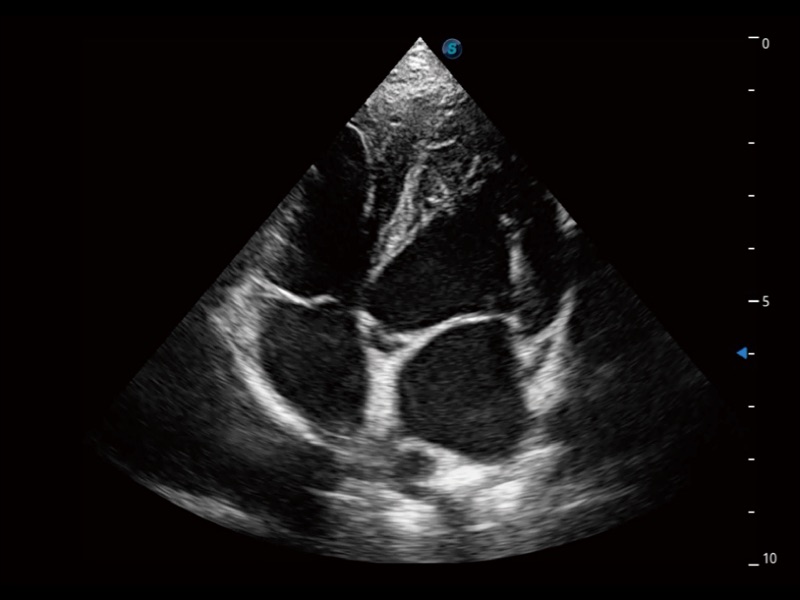

大型犬、马科、农场动物及大型异宠动物

实时用颜色表示心肌组织运动,观察和定量组织的运动情况,对快速检测与评估心肌的灌注和活性、电传导及心肌收缩和舒张功能等均能提供重要的诊断信息。

ProPet 70专为动物医生设计,对不同的动物体型和生理结构作出了针对性的优化。通过动物影像专用软件,可满足个性化的应用需求,帮助动物医生获得更精确的诊断数据。